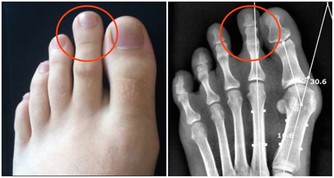

10 、皮膚變化。

美國費城福克斯蔡斯癌症研究中心腫瘤學家瑪麗·戴利博士提醒,

皮膚突然出現包塊或者色素沉著,並且變化明顯,都可能是皮膚癌的徵兆。

觀察幾周後就應該立即就醫。

另外,無論年老年輕,一旦皮膚突然出血或者出現異常剝落,也應該去看醫生。